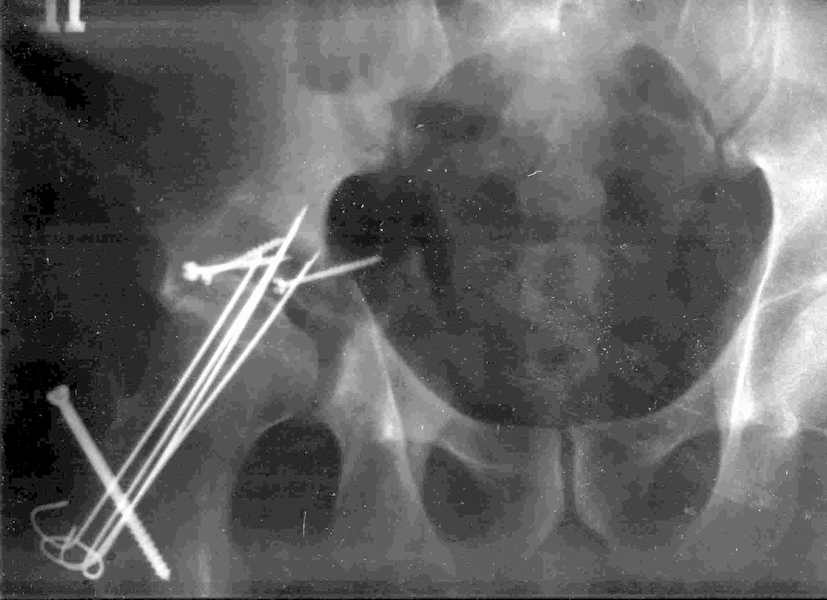

Xray1

Высылаю прямой обзорный и косой подвзошный снимки, косой запирательный неудовлетворительного качества.